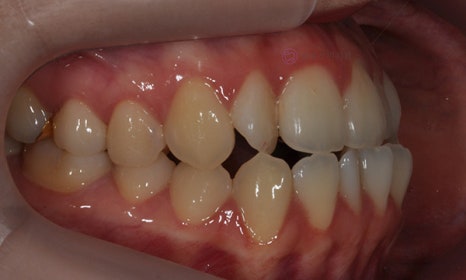

위 환자분은 치아 중심선이 맞지 않는다는 주소로 치과에 내원하셨습니다. 미소시 사진을 보면 위 치아도 오른쪽(사진 상 왼쪽)으로 틀어져 있고, 아래 치아도 왼쪽(사진 상 오른쪽)으로 틀어져 있었습니다. 그리고 양쪽 입꼬리 근육의 활성도도 차이가 있어서, 웃었을 때 왼쪽 입꼬리가 오른쪽보다 덜 올라가서 비대칭이 더 강조되어 보였습니다.

2020.7

치아 중심선의 차이를 개선하고, 얼굴의 중심과 치열의 중심을 맞춰주기 위하여 오른쪽 아래 작은 어금니를 하나만 발치하여 그 공간으로 아래 치열을 오른쪽으로 돌려주고, 위 치열은 전체적으로 왼쪽으로 치열을 이동시켜서 중심선을 맞추어 주었습니다.